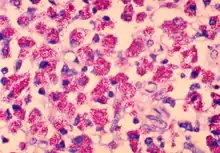

Mycobacterium avium is a species of the phylum Actinomycetota (Gram-positive bacteria with high guanine and cytosine content, one of the dominant phyla of all bacteria), belonging to the genus Mycobacterium.